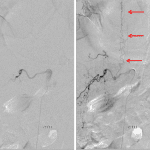

- Central cord T2/STIR hyperintensity from the levels of T5-T10 with associated mild cord expansion and possible mild enhancement

- Prominent intrathecal vessels at the level of T9-T10

- Spinal dural arteriovenous fistula

Central cord edema spanning T5-T10 with associated mild cord expansion and possible mild enhancement, which in combination with the finding of serpiginous vessels in the thecal sac at the level of T9-T10 raises concern for a dural AV fistula. Additional diagnostic considerations include cord infarct and transverse myelitis. Recommend neurosurgical evaluation and consideration of catheter angiography.